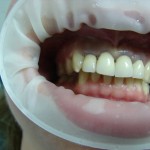

Početno stanje – plavetnilo desni.

I pored vrhunskog materijala moguće su greške. U ovom primeru bezmetalne keramike su izazvale plavetnilo desni posle četiri godine jer su zubi bili nedovoljno i nepravilno obrušeni pa je tehničar morao da napravi preširoke krunice u vratu koje su pravile hroničnu iritaciju (kao kamenac).

Poboljšanje je nastupilo kada je napravljen inter dentalni prostor – pacijentkinja se složila sa promenom postojećeg rada.